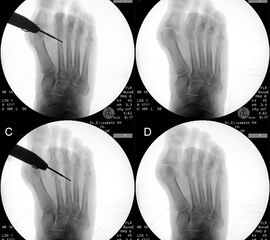

• Folgende Winkel können präoperativ zur Erleichterung der Planung am Röntgenbild eingezeichnet werden:

• IMW (Intermetatarsalwinkel).

• HVW (Hallux valgus-Winkel).

• DMAA (Distal Metatarsal Articular Angle) – Planung der ggf. notwendigen Reverdin-Isham-Osteotomie.

• PPAA (Proximal Phalangeal Articular Angle) – Planung der ggf. notwendigen Akin-Osteotomie.

• VAW (Vorfußadduktionswinkel) – Planung der Ausrichtung der DMMO (Distalen minimalinvasiven Metatarsale Osteotomien).

Einschränkend ist anzumerken, dass o.g. Winkel projektions- und rotationsabhängig sind 15. Daher ist intraoperativ die Planung anhand von Bildverstärkeraufnahmen zu verifizieren und ggf. anzupassen.

Zum Lesen der Bildbeschreibung und zur Vollansicht bitte die Bilder anklicken.

In unserer prospektiven Studie wurden 10 Patienten (8 Frauen und 2 Männer; Ø Alter 58 ¼ Jahre) mit einem symptomatischen Hallux valgus bei Pes adductus und Metatarsalgie mittels einer Lapidusarthrodese und einer lateralisierenden DMMO versorgt. Die Fusion des TMT-I-Gelenkes erfolgte offen mittels einer winkelstabilen, plantaren Platte. Alle zusätzlichen distalen Eingriffe (DMMO, Isham-OT, Akin-OT, Kleinzehenkorrekturen) wurden in minimalinvasiver Technik durchgeführt. Die Patienten wurden nach 6 Monaten klinisch und radiologisch nachuntersucht.

Der präoperative AOFAS-Score betrug 41,5 Punkte und konnte postoperativ auf durchschnittlich 86,2 Punkte verbessert werden (p<0,005). Der IMW reduzierte sich von Ø 16,7° (8,5°-20,3°) präoperativ auf Ø 7,14° (6,1°-9,5°) (p<0,005). Ebenso konnte der HVW von präoperativ Ø 45,2° auf postoperativ Ø 9,4° (p<0,005) korrigiert werden. Durch die Durchführung der modifizierten, lateralisierenden DMMO veränderte sich der präoperative VAW von Ø 23° (19,3°-33,5°) auf Ø 15,6° (13°-17,2°; p<0,004).